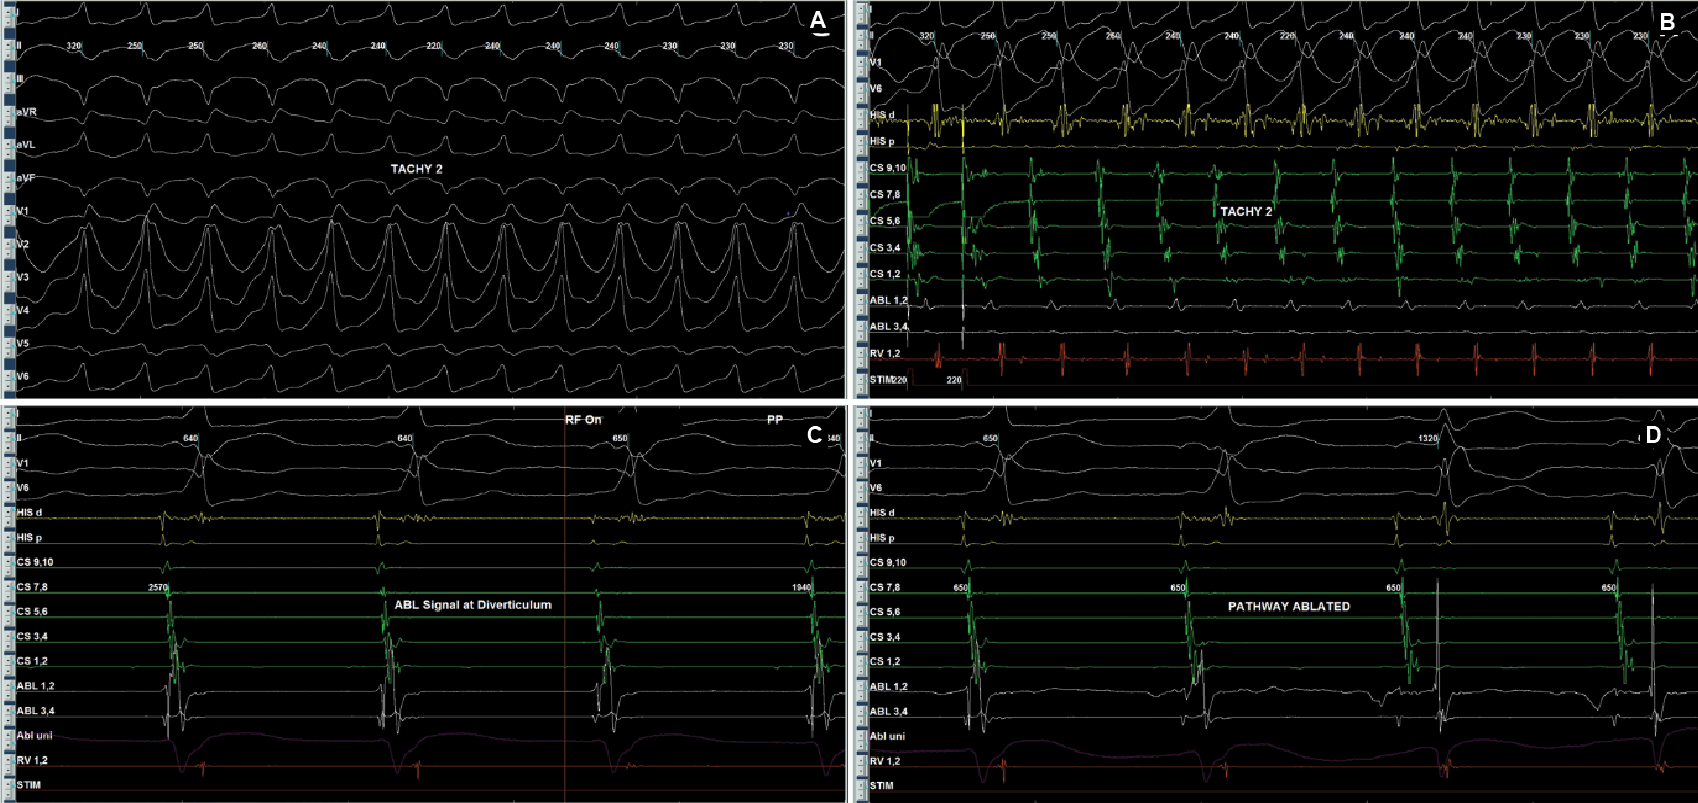

Later on, during programmed atrial stimulation with burst pacing, patient developed another broad complex tachycardia (TCL = 220 ms) with 1:1 AV relationship. The tachycardia was hemodynamically unstable and led to ventricular fibrillation and required direct current cardioversion (DCCV) with 200J (Fig. 4). With the help of steerable ablation catheter, earliest atrial activation during ventricular pacing and earliest ventricular signal in sinus rhythm was mapped at the septal tricuspid annulus (RA mapping) and septal mitral annulus (LA mapping). Afterwards coronary sinus angiogram was taken, which showed a coronary sinus diverticulum near the decapolar coronary sinus 5-6 electrodes (Fig. 5). Radiofrequency applications were delivered at the neck of diverticulum that leads to disappearance of pre-excitation (Fig. 6). Afterwards aggressive programmed stimulation done on and off with isoproterenol that did not induce any atrial arrhythmias.

Figure 4. Antidromic tachycardia (A and B) involving posteroseptal pathway. EGMs recorded (C) inside diverticulum neck that was ablated successfully (D).